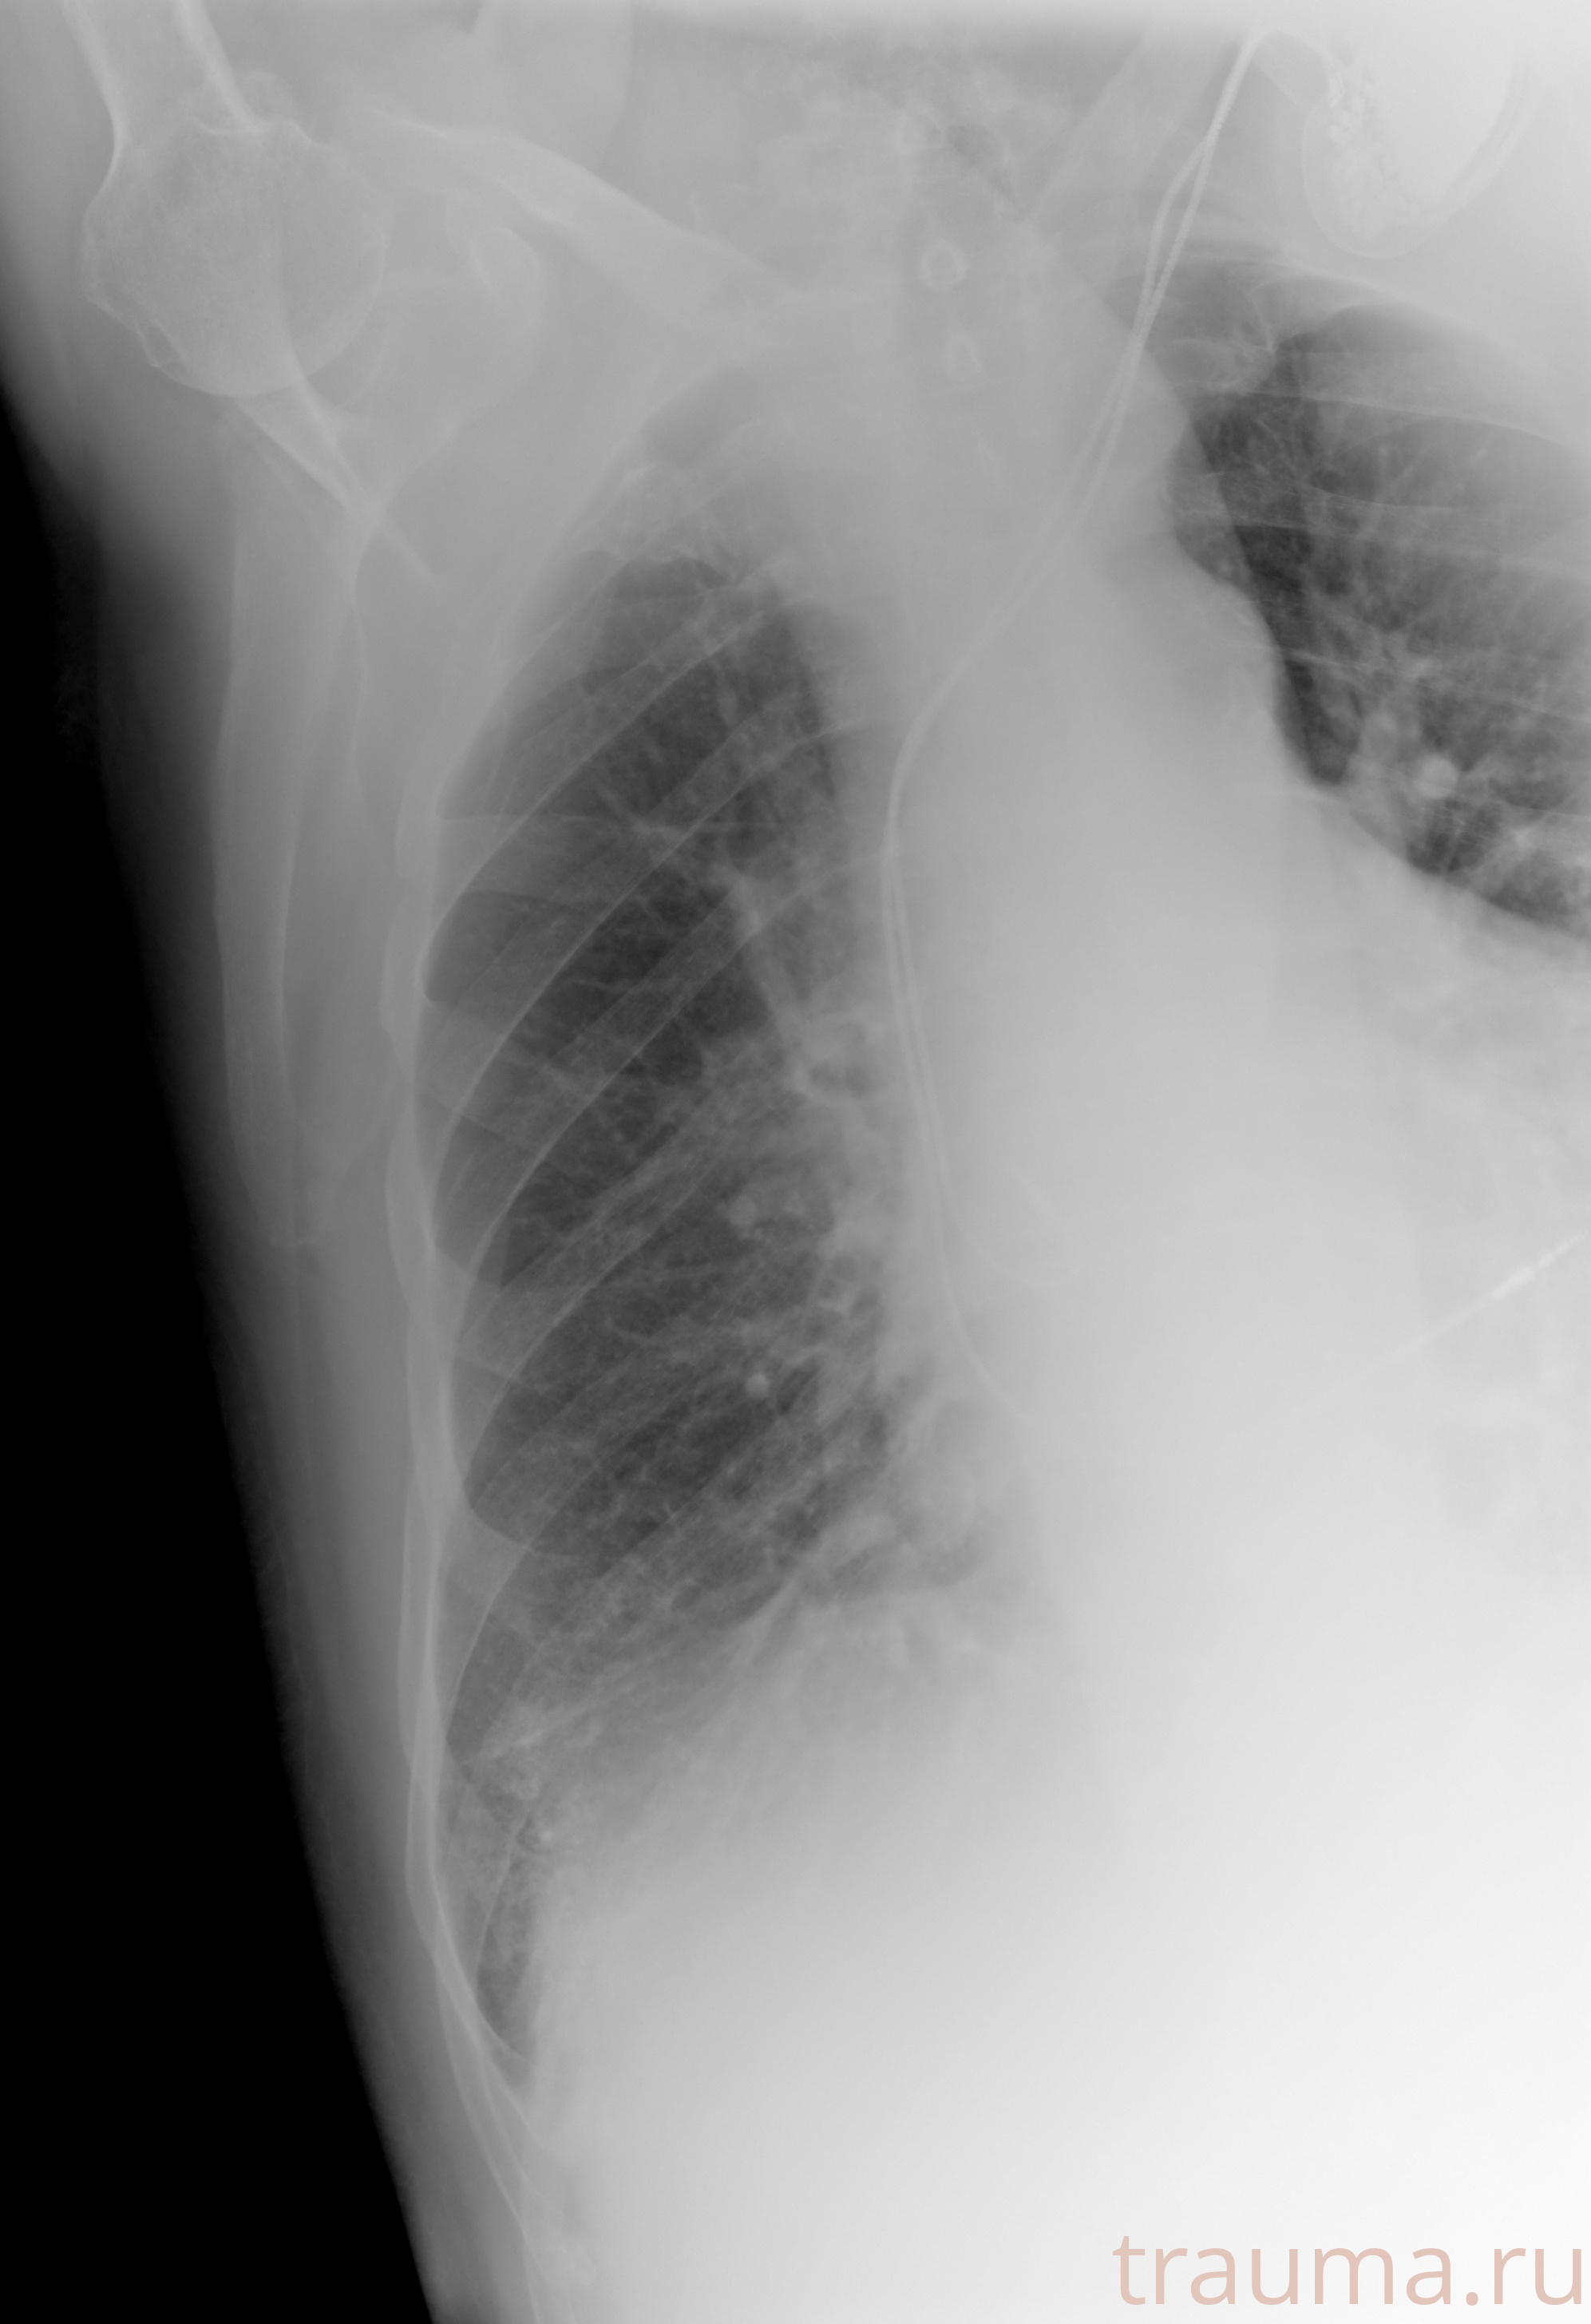

Рентген на дому: по вашему адресу приезжает врач-рентгенолог, травматолог-ортопед с мобильным рентгеновским аппаратом, проводит диагностику травмы или заболевания, делает необходимые рентгенограммы, дает рекомендации по дальнейшему лечению. Получить качественные снимки в домашних условиях возможно благодаря уникальной методике, разработанной МосРентген Центром для института  Склифосовского